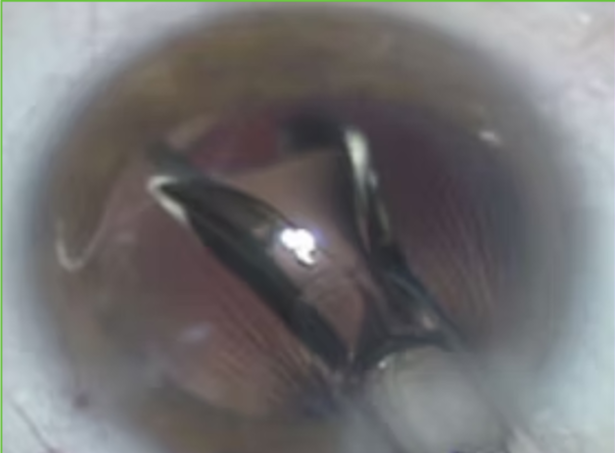

Facoemulsificação Aspirando

Implante da Lente Injetável

Abertura da Lente

Término da Cirúrgia